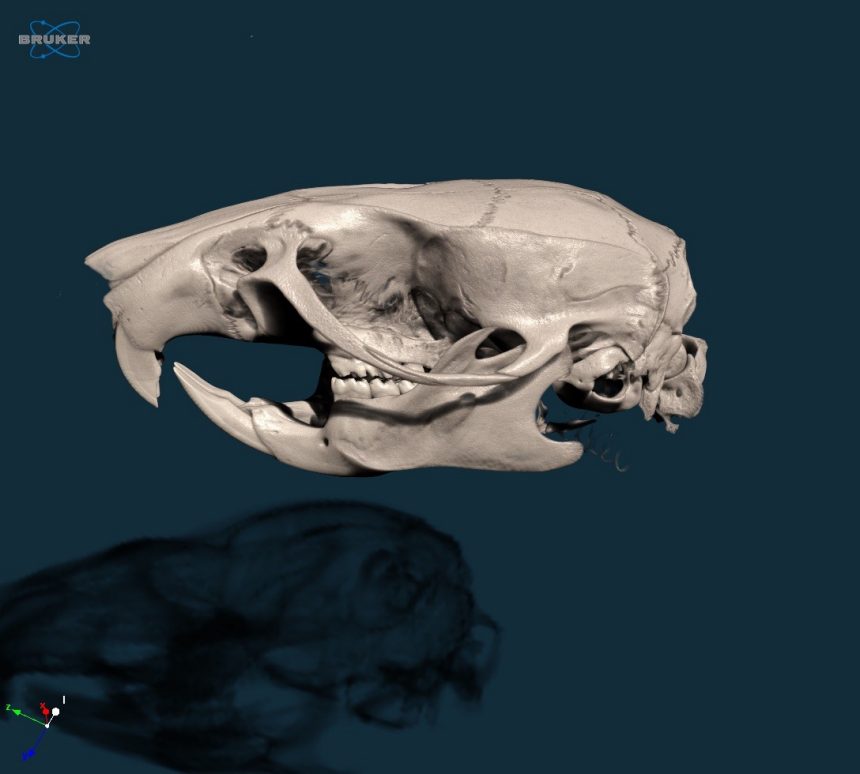

2. 3D model of a rat skull, scanned at 20um voxel size in vivo

2.jpeg